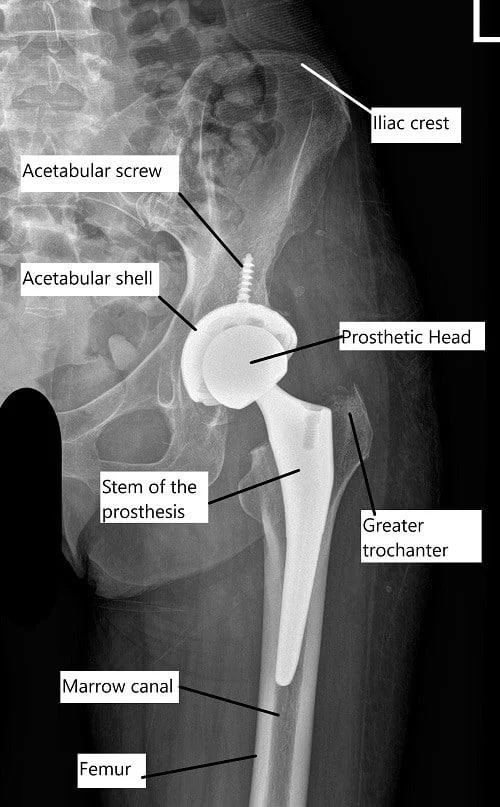

Hip Joint Prosthesis

Total Hip Replacement implants can be categorised into two broad segments:

1. Femoral Component

Stem

Head

• The head is attached to the neck of the stem through “Morse Taper Locking”.

2. Acetabular Component

Uncemented

• Consists of a shell made of titanium alloy with porous coated surface, allowing bone growth.

• Liner: Highly cross-linked polyethylene (XLPE) & Ceramic liners.

Usual duration of surgery is 90-100 mins. The surgery principally aims at precise resection of diseased femoral head, serial reaming of acetabulum for preparation for acetabular cup & serial broaching of femoral canal for femoral stem.

The Acetabular Cup is implanted into reamed acetabular cavity followed by placement of designated liner (Highly Crosslinked PE/ Ceramic).

The femoral stem is implanted into broached femoral canal. Trialling is performed for judicious selection of most appropriate size ensuring adequate restoration of offset & limb length with assessment of stability & impingement free ROM.

Final Head size is selected & implanted onto Femoral Stem (Metal/ Ceramic/ Oxinium). After final reduction closure of soft tissue sleeve is done with Ethibond No 5. Wound is closed in layers using absorbable sutures & skin with staplers. Occlusive dressing applied.